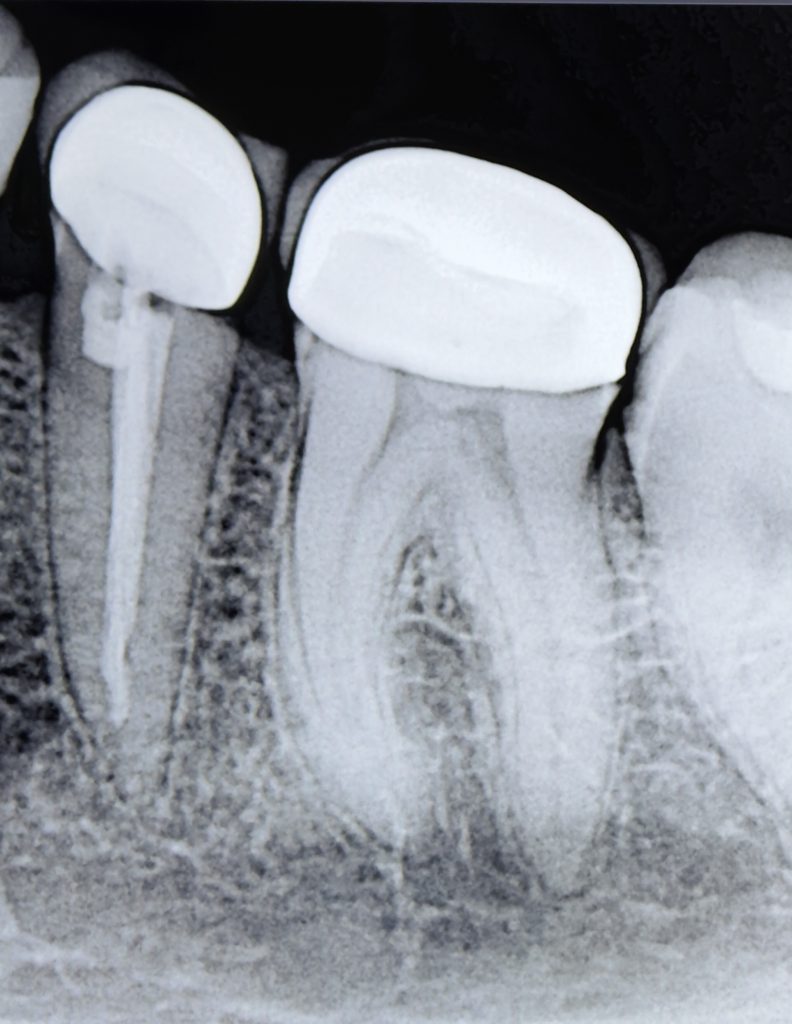

4. Obturation

Obturation performed with Bioceramic Sealer (Endo Sequence BC) and warm vertical condensation to ensure apical seal and coronal adaptation (Fig 3).

7. Post-Operative Evaluation

Radiograph confirmed ideal obturation, core adaptation, and marginal integrity (Fig 3). The final restoration blended esthetically and functionally with the dentition (Fig 5).

- Fig 3: Post-obturation radiograph confirming dense 3-D fill.